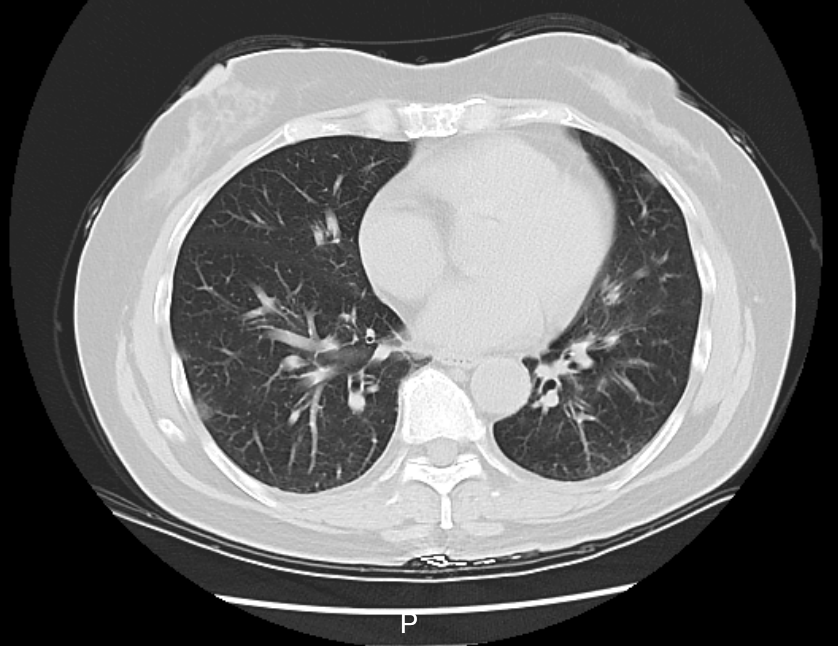

△李阿姨肺部CT影像

家中同行的6个人,有5个人都先后发烧了。检测结果显示,李阿姨得了病毒性肺炎,甲型流感病毒核酸呈阳性。经治疗,已有明显好转。